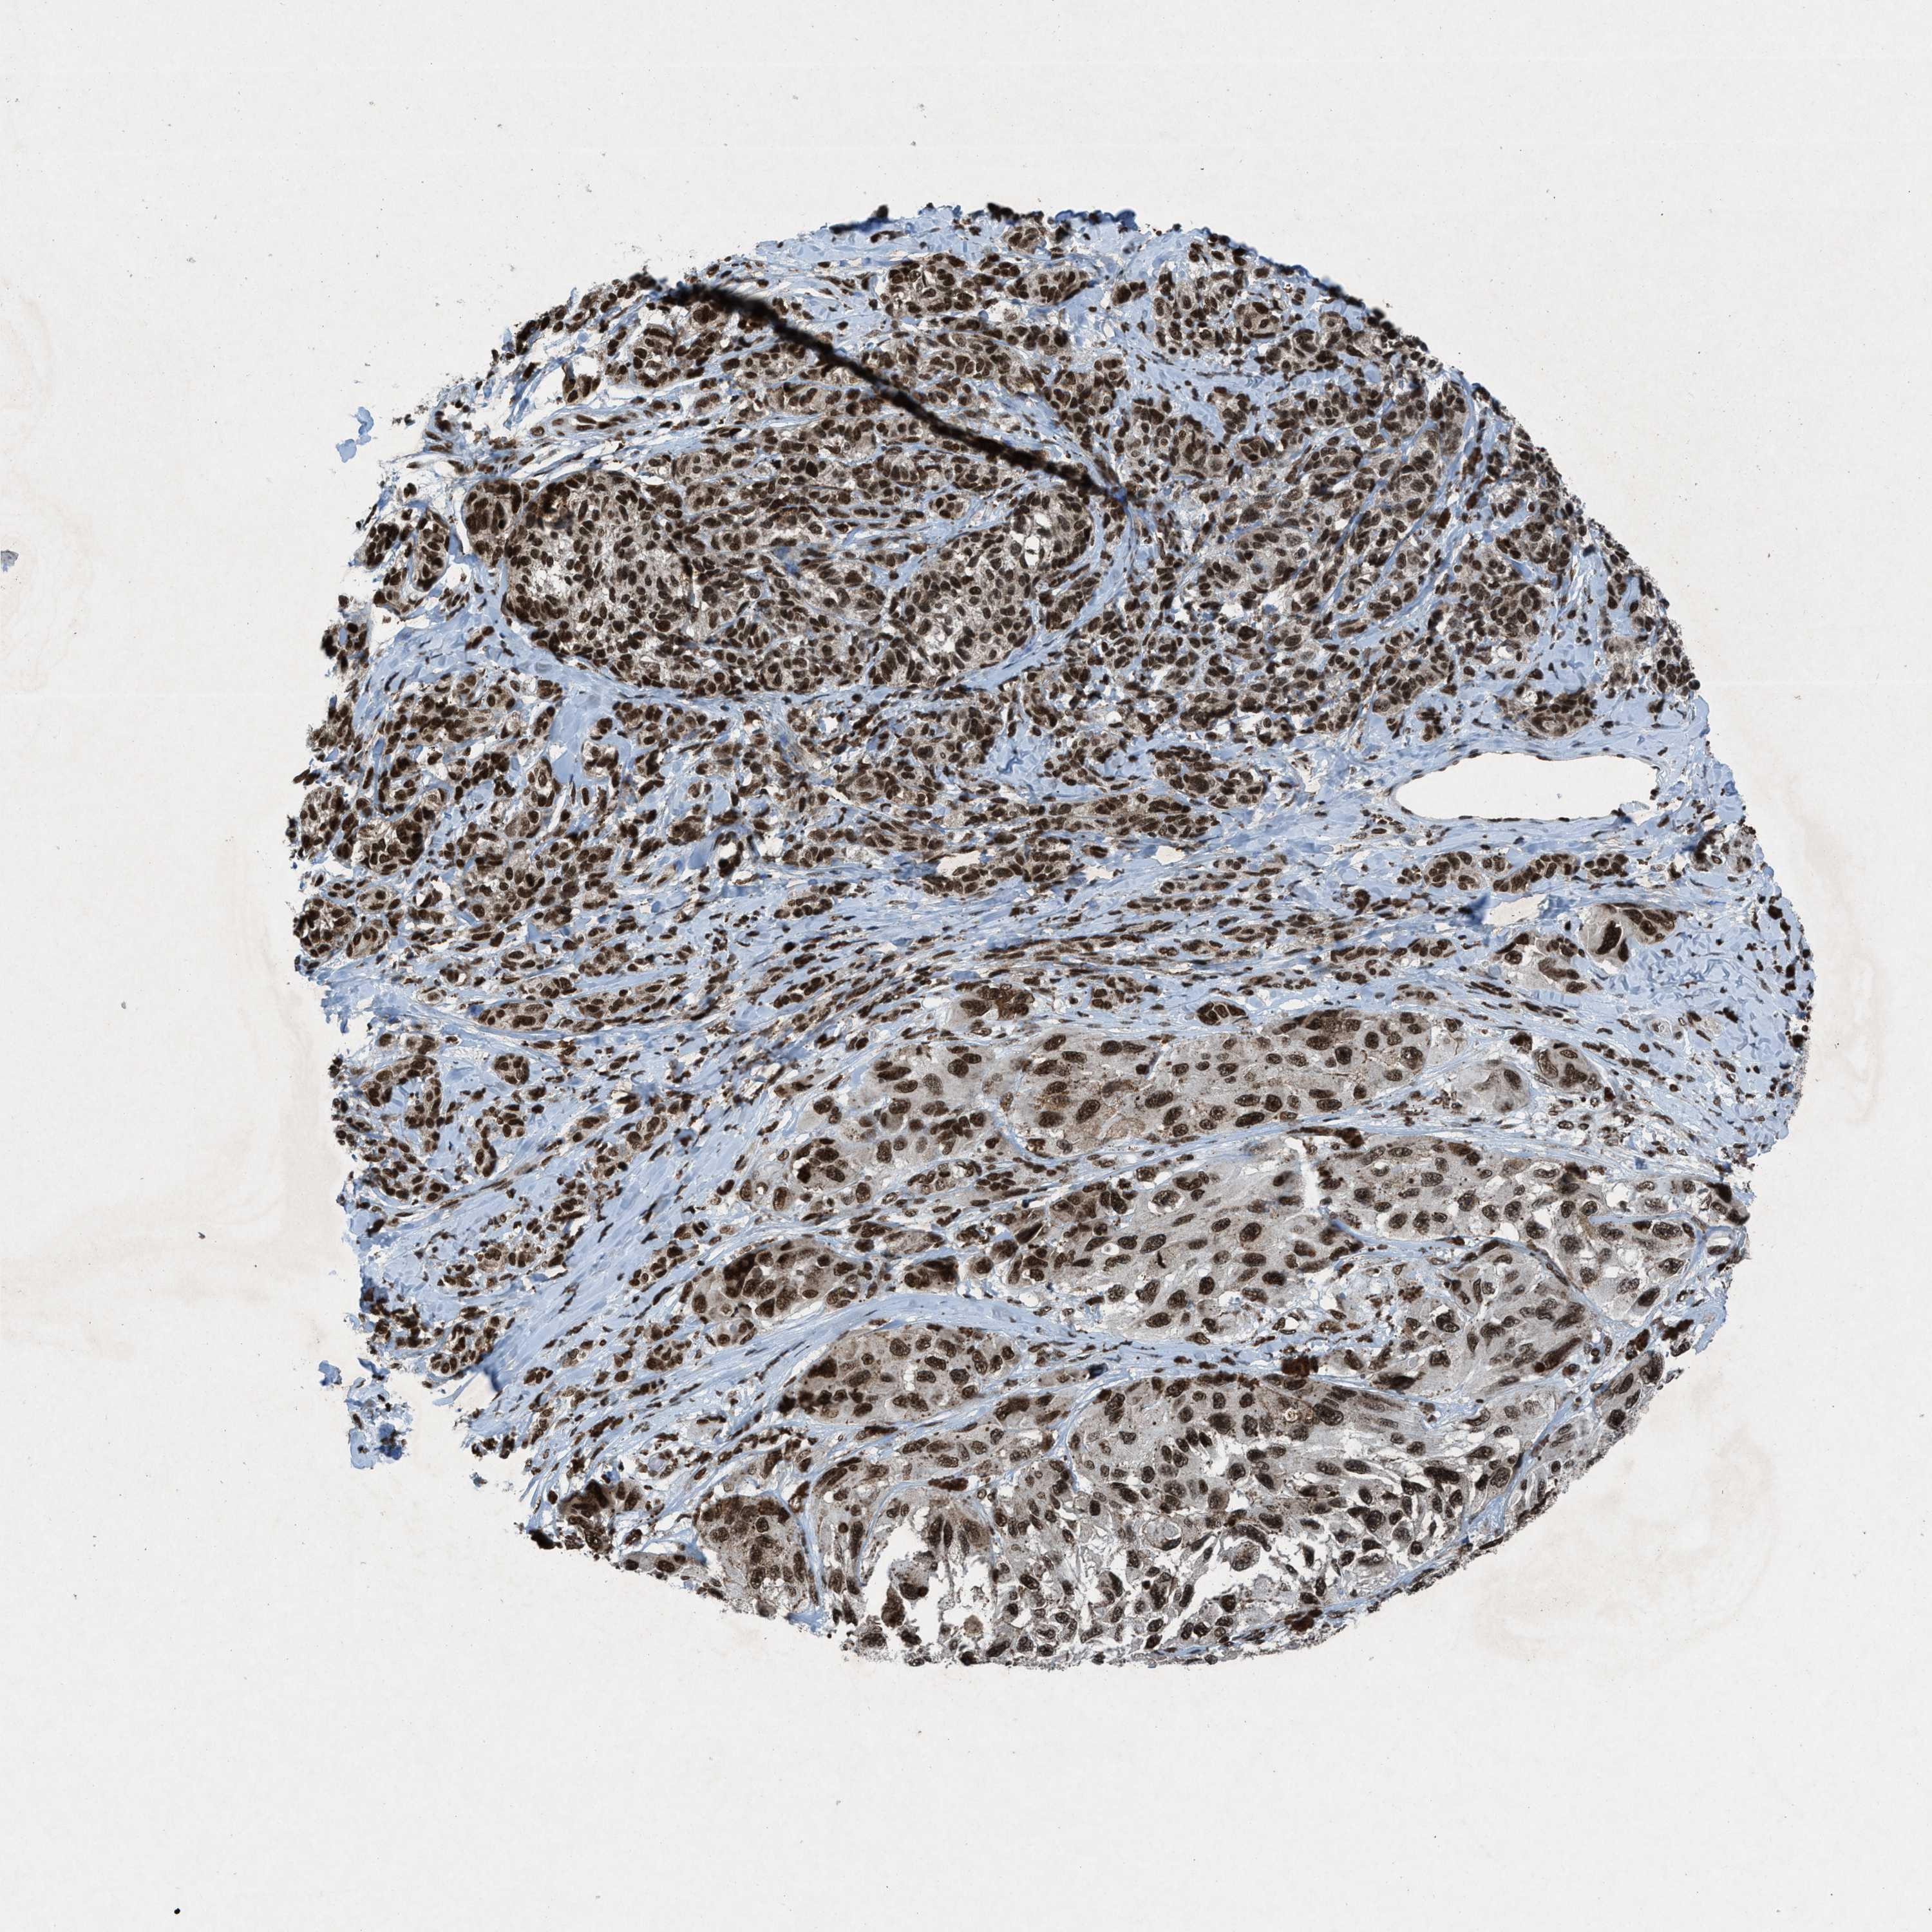

MELANOMA - Protein expressioni

A mouse-over function shows sample information and annotation data. Click on an image to view it in a full screen mode. Samples can be filtered based on level of antibody staining by selecting one or several of the following categories: high, medium, low and not detected. The assay and annotation is described here.

Note that samples used for immunohistochemistry by the Human Protein Atlas do not correspond to samples in the TCGA dataset.

Antibody stainingi

Antibody staining in the annotated cell types in the current human tissue is reported as not detected, low, medium, or high, based on conventional immunohistochemistry profiling in selected tissues. This score is based on the combination of the staining intensity and fraction of stained cells.

Each image is clickable and will lead to virtual microscopy that enables deeper exploration of all samples and also displays staining intensity scores, fraction scores and subcellular localization as well as patient and tissue information for each sample.

Antibody HPA061593

Antibody CAB016327

Staining

High

Medium

Low

Not detected

Intensity

Strong

Moderate

Weak

Negative

Quantity

>75%

75%-25%

<25%

None

Location

Nuclear

Cytoplasmic/membranous

Cytoplasmic/membranous,nuclear

Malignant melanoma, NOS

Malignant melanoma, Metastatic site